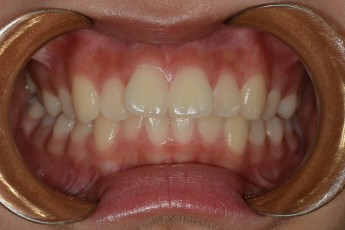

Before

After